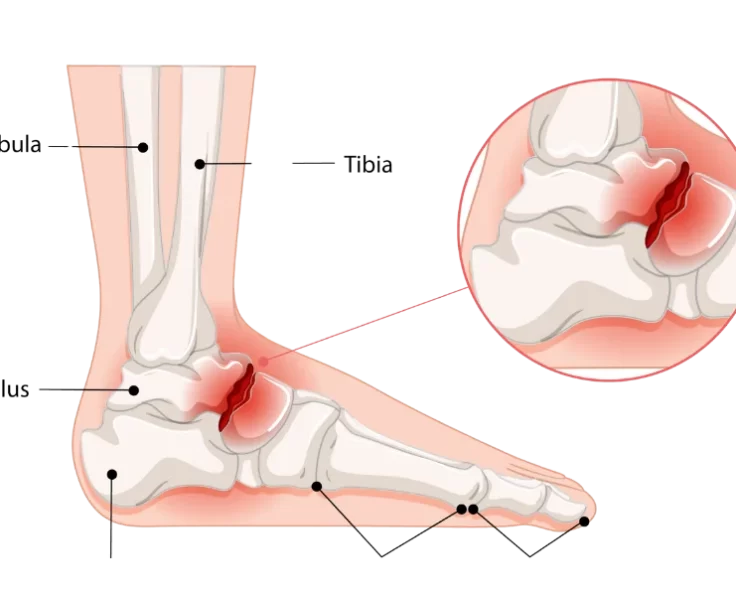

Complex Upper Limb Fractures

Fractures and dislocations of the arms and shoulders are known as upper limb fractures and dislocations.